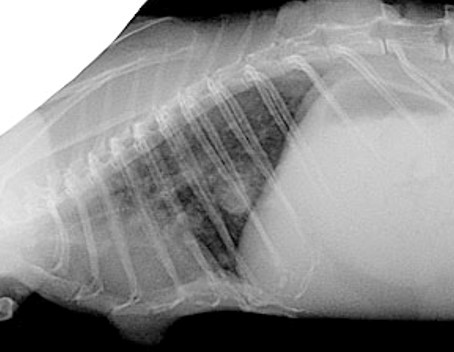

画像検査

胸部X線写真で肺結節または肺浸潤、胸水、頭蓋縦隔腫瘤などの様々なリンパ腫に関連した異常が認められます。腹部超音波検査では、腸間膜リンパ節の腫大、胃腸の局所的肥厚や腫瘤、脾腫などの異常も確認されます。超音波検査は診断用サンプルを採取するための細針吸引を容易にするのにも特に役立ちます。